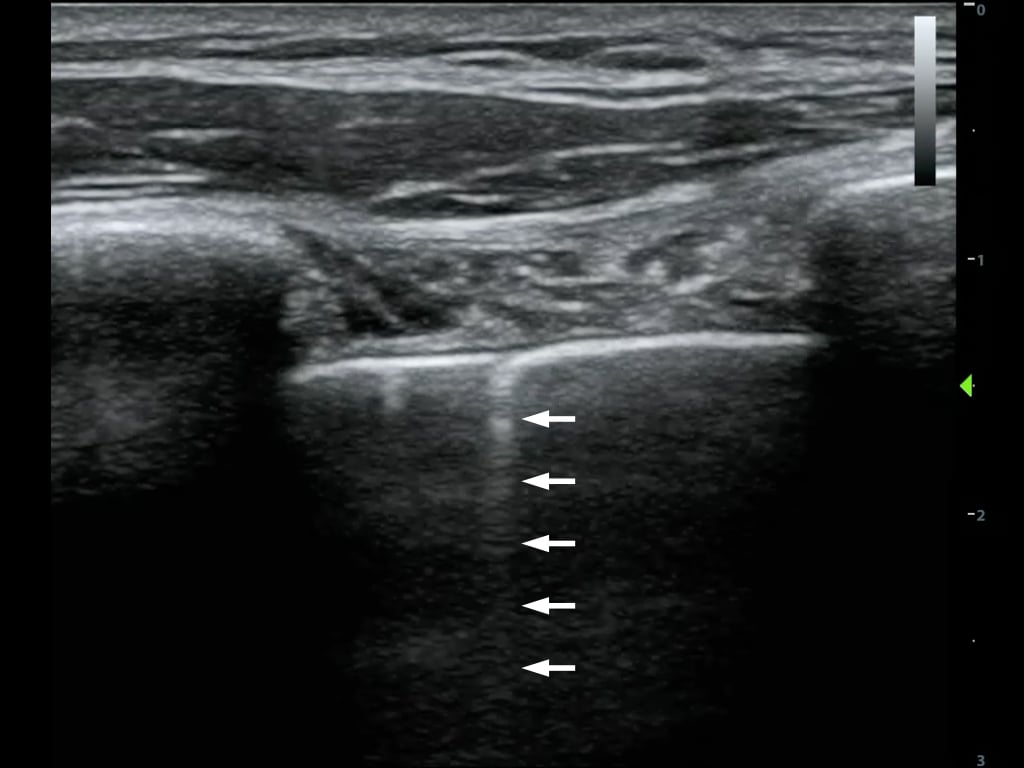

- Comet Tail Artifact is similar to reverberation.

- It is produced by the front and back of a very strong reflector (air bubble, BB gun pellet)

- The reverberations are spaced very narrowly and blend into a small band (Figure 10)

- Figure 10. Comet tail artifact from the pleural line